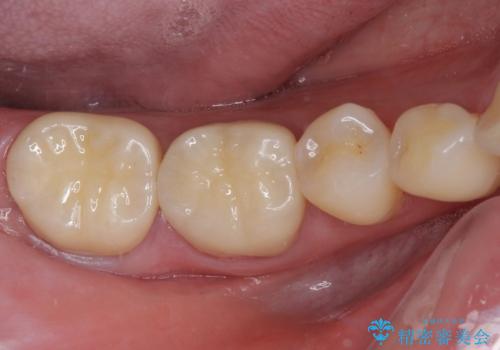

奥歯の壊れたり汚れたりしたクラウン オールセラミッククラウンによる審美歯科治療